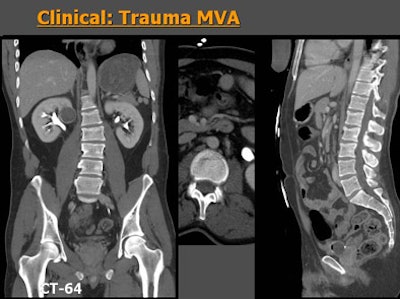

![]() |

| Sixty-four-row MDCT images of a patient who suffered a moving vehicle accident. Axial images (above) show a very subtle line seen by one observer but missed by a second reader. However, MPRs (below) clearly show vertebral fractures at L1 and L2, adding significantly to the value of the scan -- perceived value of MPR was rated 4. |